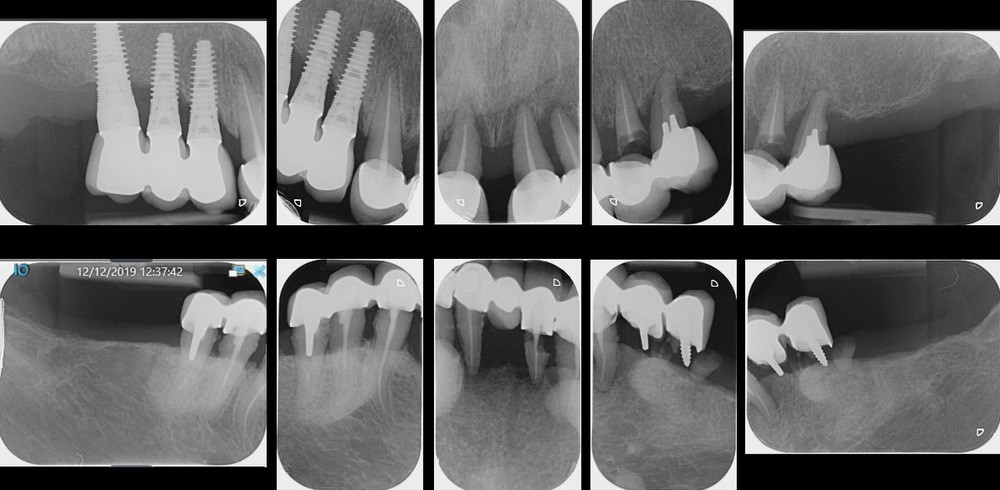

Les examens cliniques et radiographiques permettent de diagnostiquer de nombreuses reprises de caries sous les prothèses existantes, une parodontite chronique terminale, associée à de nombreuses migrations dentaires, posant l’indication de l’avulsion de l’ensemble des dents maxillaires (fig. 2).

Les implants du secteur 1 présentent…